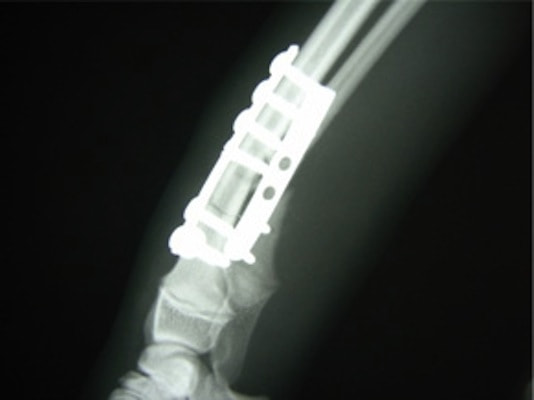

Matrix MANDIBLE

AO/ASIFコンセプトのもとに解発された人医用のロッキングプレートシステムです。材質がチタン製で、10°〜15°の角度をつけてロッキングスクリューの設置が可能であり、制限された部位での強固な固定に優れています。

脊髄の減圧、脊柱管の再構築・安定化を目的に、片側椎弓切除術およびMatrixMANDIBLE Plateによる椎体固定を実施しました。

隣接椎体を架橋するようにプレートを設置しました。

術後レントゲン写真